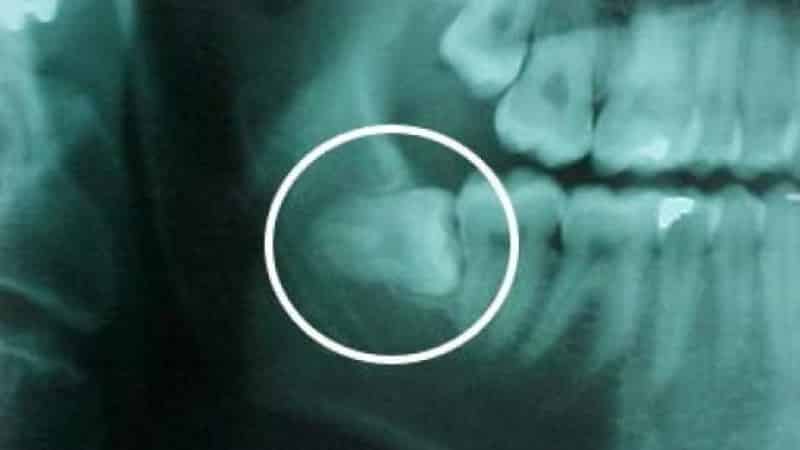

Если внешние признаки воспаления отсутствуют, рекомендуется сделать рентген, чтобы заранее оценить правильность роста зуба и определить необходимость его удаления.

В таких случаях крайне важно незамедлительно обратиться к стоматологу для проведения рентгенографического исследования и назначения лечения или, при необходимости, удаления зуба, чтобы избежать дальнейших осложнений.

- ретинированный зуб мудрости, который неправильно расположен в челюсти и не может прорезаться из-за частичного или полного упирания в соседние зубы;